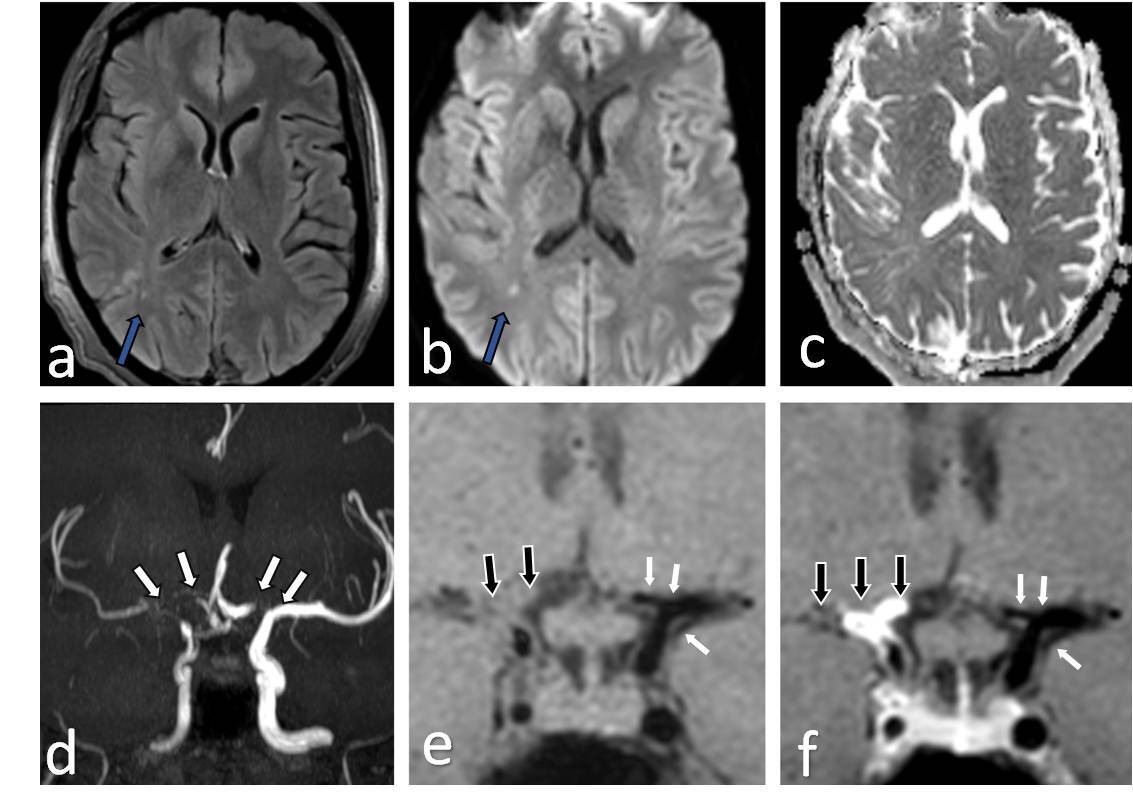

Figure 4

Two-year-old female presenting with left hemiparesis and seizures. Axial T2 (A), axial diffusion-weighted imaging (DWI) (B) and axial apparent diffusion coefficient (ADC) map (C) images show volume loss with encephalomalacic changes in left fronto-parietal region (white arrows in A) along with acute infarct involving right fronto-parietal lobe with diffusion restriction (blue arrows in B and C). Axial maximum intensity projection time-of-flight magnetic resonance angiography (MRA) image (D) shows stenotic bilateral supraclinoid internal carotid artery (ICA), right terminus ICA, occluded left terminus ICA, B/L anterior cerebral artery (ACA), B/L middle cerebral artery (MCA) with normal B/L posterior cerebral artery (PCA) and distal basilar artery (BA) (white arrows in D). Axial (E) and coronal post-contrast vessel wall imaging (VWI) (F) showing vessel wall thickening and grade 1 concentric enhancement of B/L supraclinoid ICAs (black arrows in E) with grade 1 concentric enhancement in bilateral PCA and distal BA (small white arrows in E and F)